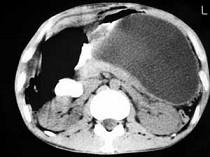

问题 男,33岁,腹部外伤后两月余,腹部疼痛,行CT扫描所见如图,最可能的诊断是 ( )

选项 A.急性胰腺炎 B.慢性胰腺炎 C.胰腺创伤性假性囊肿 D.畸胎瘤 E.腹腔包裹性积血

答案 C